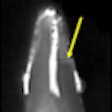

SWIFT MRI shows promise for endodontics